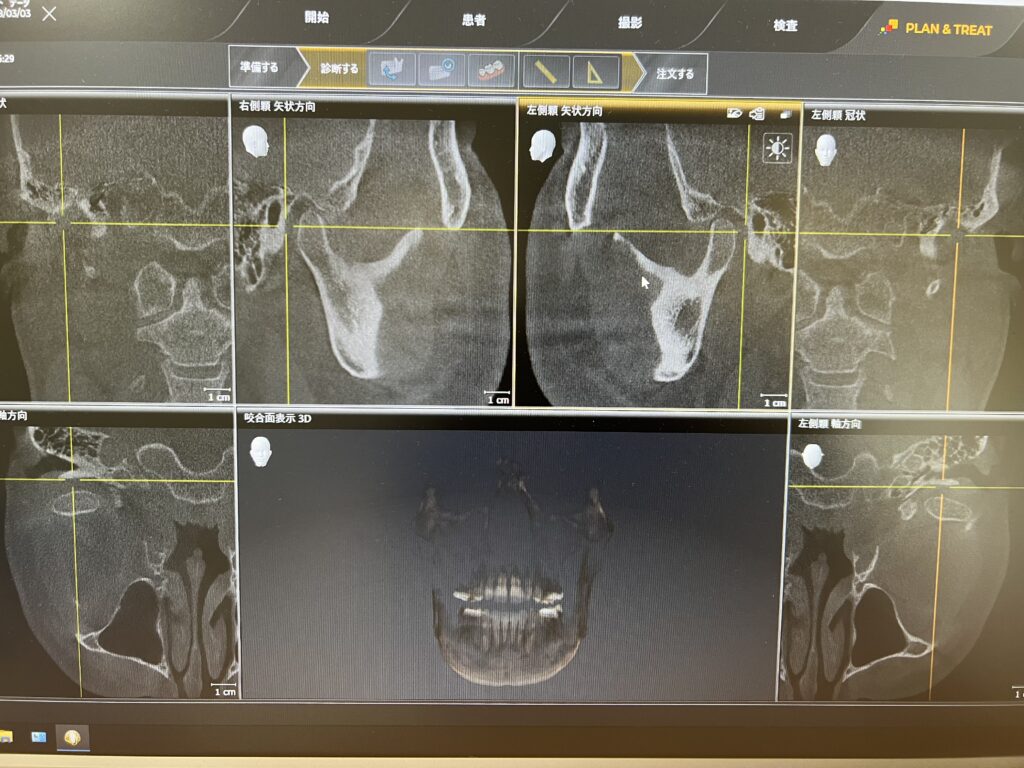

顎関節の状態や、矯正の際に骨格を診断するセファロ撮影なども可能です。

このように撮影範囲が広いので顎関節の形態の確認もできます.

他にCT撮影ではないですが、今回セファロと呼ばれる規格写真撮影もオプションで取り付けて撮影が可能となっているので

このようなレントゲン撮影も可能で、骨格的な問題を考えて矯正治療などを行います。